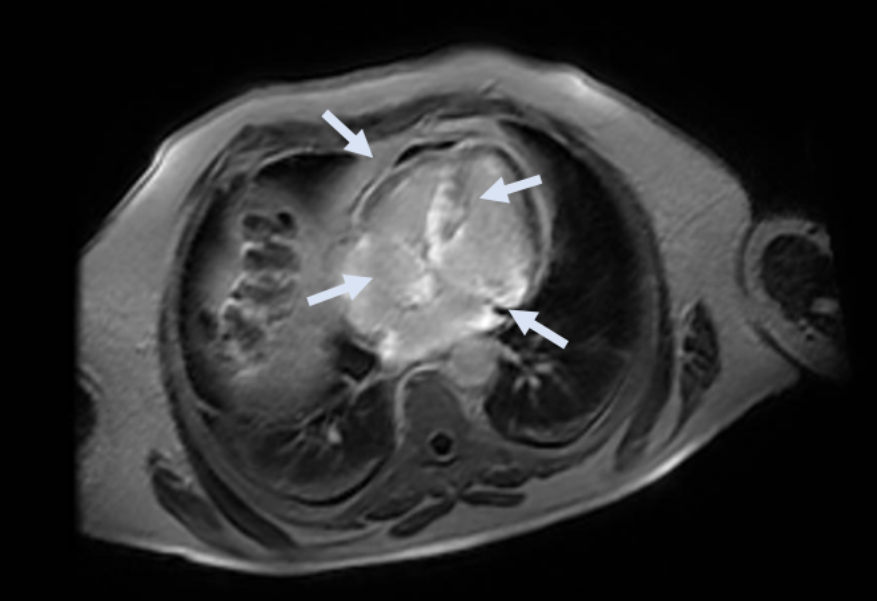

Kardiale MRT (CMR) zur weiteren Abklärung

Angesichts der elektro-anatomischen Diskordanz und des im Echokardiogramm festgestellten hypertrophen Phänotyps wurde eine CMR durchgeführt. Die Ergebnisse:

• biventrikuläre Hypertrophie mit erhaltener systolischer Funktion;

• infiltratives Muster mit ausgedehnten Bereichen von spätem Gadolinium-Enhancement (LGE) vorwiegend intramyokardial auf Höhe des basalen und mittleren Septums, der basalen postero-lateralen Wand, der Papillarmuskeln und an der subepikardial-intramyokardialen Stelle der vorderen mittleren basalen Wand und der inferioren Wand;

• Vorhandensein von LGE auch auf Höhe der Vorhofwände und des verdickten interatrialen Septums;

• außerdem Vorhandensein einer veränderten Gadoliniumkinetik, die durch eine schnelle Aufnahme des Kontrastmittels in das Myokard auf Kosten des Blutes in den Herzkammern gekennzeichnet ist.

• CMR: ventrikuläre Hypertrophie, veränderte Gadoliniumkinetik und diffuser LGE-Befund mit nicht-ischämischem Muster, der auch die Herzvorhöfe betrifft.